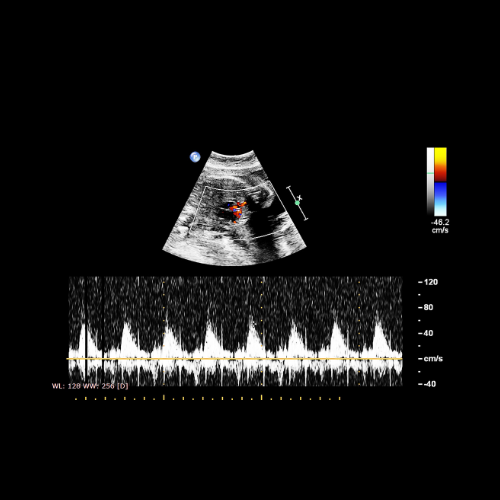

- Evaluates blood flow using Doppler studies

- Doppler Flow Studies: Umbilical artery, middle cerebral artery, ductus venosus